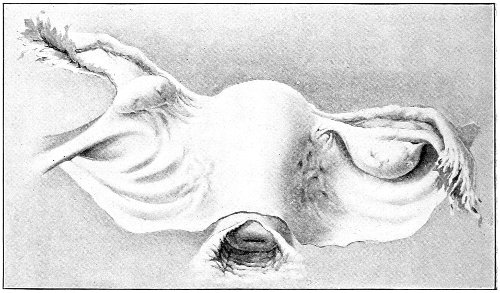

An accurate knowledge of the anatomy and mechanism of the female perineum is essential to an understanding of the nature and treatment of injuries to this structure. The anatomical structures lying between the anus behind and the symphysis pubis in front are those that most directly interest the gynecologist. Proceeding from 57 below upward, we find the following structures lying in superimposed planes: the skin, the superficial fascia, the deep layer of the superficial fascia, the transversus perinæi and the sphincter vaginæ muscles, the anterior layer of the triangular ligament, the posterior layer of the triangular ligament, the levator ani muscle (Fig. 19).

The vagina passes through these structures. They surround and support the ostium vaginæ as the fascia and muscles surround and support the opening of the rectum or the anus. The muscles and fasciæ are attached in the median line between the anus and the vagina, and therefore this part of the body, which is called the perineum, is supported or maintained in its 58 proper position by these various structures. The transversus perinæi arises from the ramus of the ischium and is inserted in the perineum. The bulbo-cavernosus, or sphincter vaginæ, arises in the perineum and is inserted in and about the clitoris. The inner fibers of the levator ani arise from the symphysis pubis and are inserted in the perineum and the lower part of the vagina (Fig. 20). When these muscles contract, their action, therefore, is to draw the perineum upward and forward. At the same time the anus is drawn upward and forward, and so also is the posterior margin of the ostium vaginæ and the lower portion of the posterior vaginal wall.

The vagina has no circular sphincter like the anus, but 59 the vaginal month is kept closed by the action of the transversus perinæi, sphincter vaginæ, and levator ani muscles, which draw the perineum forward, and thus keep the posterior vaginal wall in apposition with the anterior wall.

This sling of muscles and fascia, which surrounds and supports the opening of the vagina, may readily be felt in the nulliparous woman by introducing the finger in the vagina and pressing backward and outward toward the ischio-rectal fossa. We then feel plainly, immediately within the ostium vaginæ, a firm resisting band of tissue, apparently about half an inch broad, embracing the posterior portion of the lower vagina. This band is formed by the inner edges of the various muscles and planes of fascia that have been described.

The vagina extends, as a transverse slit in the pelvic floor, upward and backward, approximately in the direction 60 of a line drawn from the ostium vaginæ to the fifth sacral vertebra. It is approximately parallel with the conjugate of the brim, so that when the woman is erect the long axis of the vagina is inclined at an angle of 60° to the horizon. The vagina is not a vertical open tube: it is a slit in the pelvic floor, in health always closed by the accurate apposition of the anterior and posterior walls (Fig. 21). The anterior vaginal wall is about 2½ inches long in a vertical mesial line. The posterior vaginal wall is about 3½ inches long. The vaginal walls are triangular in shape, being broader above than below. The shape of the normal vagina at the pelvic outlet is shown by Fig. 23. The section here shows the vaginal 61 slit of the shape of the letter H. The portions of the slit extending backward and somewhat outward are called the vaginal sulci or furrows. They are directions of diminished resistance in which tears are liable to occur.